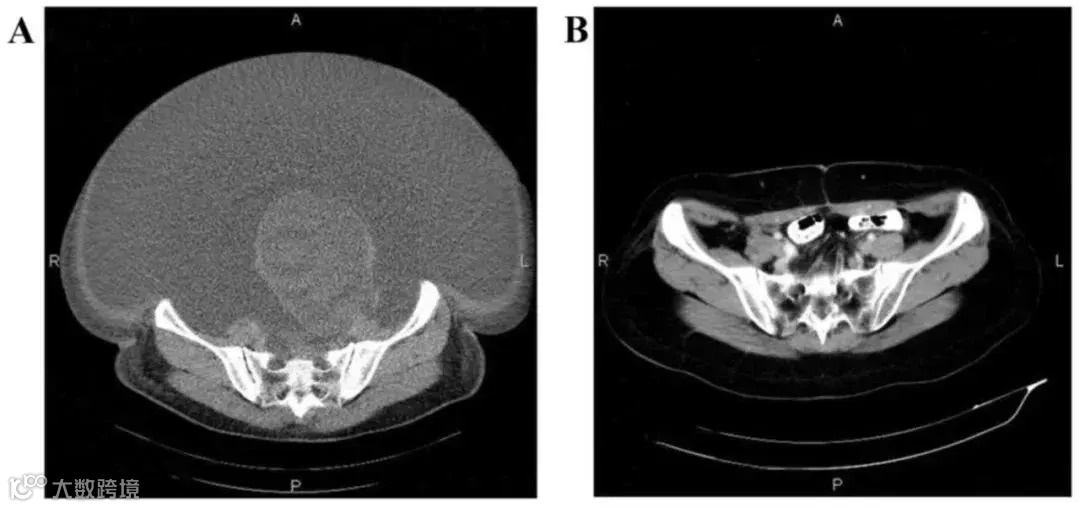

案例2:国内一名60岁的卵巢癌晚期患者,在接受了体外扩增,高度活化的同种异体NK细胞的临床治疗后,CA125水平从11,270降至580,所有腹水都消失了。此外,CT扫描的肿块体积减小,并且没有出现副作用。